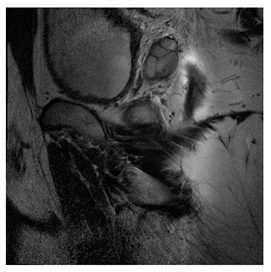

Breast-MRI-NACT-Pilot is an MRI-type image database, collecting breast medical images of 64 patients. Some samples are shown in Figure 12a.

Figure 12.

Sampled images in the tested benchmark databases: (a) Breast-MRI-NACT-Pilot (breast), (b) ACRIN-DSC-MR-Brain (brain), (c) NIH (chest), (d) Lung-PET-CT-Dx (lung), (e) Prostate-MRI (prostate), and (f) Other grayscale standard images.

- Prostate-MRI Database (available at: https://wiki.cancerimagingarchive.net/display/Public/PROSTATE-MRI (accessed on 4 November 2021))

Prostate-MRI database contains MRI-type medical images and collects prostate medical images. Some samples are shown in Figure 12e.

In this subsection, we describe three experiments used to measure the performance of the proposed method. The first experiment shows the stegoimage and marks the pixels’ positions that have been modified during the embedding process, as shown in Table 2, Table 3, Table 4, Table 5, Table 6 and Table 7. To make modified pixel positions have a pronounced effect, we set bpp (bit per pixel) rate at 0.05 and 0.025. It can be seen from the results that the proposed local complexity function can distinguish ROI and RONI from most of the medical images, so modified pixels are mainly gathered in RONI. However, it is observed that the proposed local complexity function cannot distinguish between ROI and RONI in the Prostate-MRI database due to the relative complexity of the image. Besides, “Modified BPP” represents the proportion of pixels in the image that have been modified. We observed that the performance of “baboon” in the grayscale standard images database is poor because that image’s pixels are relatively complex. It becomes challenging to select the more embeddable pixels based on the proposed local complexity function. Nevertheless, the modified pixel positions in other grayscale standard images, such as Lena and Barbara, are relatively smooth, verifying that our local complexity function is also applicable to general images.